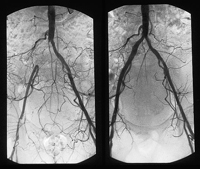

La cirugía endovascular procura, mediante catéteres, solucionar problemas de accesos pequeños o estrangulaciones de vasos, sobre todo aneurismas o estenosis, en particular ilíacas o aortoilíacas. Cirugía endovascular Después de una dirección hacia los tratamientos invasivos que caracterizó el desarrollo de la cirugía del siglo XX, fue surgiendo a finales de este siglo una tendencia a realizar los tratamientos en forma menos invasiva en todas las especialidades quirúrgicas. El gran avance tecnológico impulsó y favoreció estos cambios, desarrollándose técnicas de cirugía video-asistidas y de cirugía percutánea.

La Cirugía Endovascular consigue la resolución de muchos casos de enfermedad vascular (estenosis, oclusiones, aneurismas, fistulas...) con un simple abordaje percutáneo. Mediante la introducción de guías y catéteres a través de un vaso, habitualmente la arteria femoral, que sirven de transporte a balones de dilatación, endoprótesis.... el paciente se beneficia de las ventajas de una anestesia local, una técnica menos agresiva y un postoperatorio más corto y confortable; en muchas ocasiones pueden realizarse en hospital de día o con ingreso de 24 horas.

Muchos de estos métodos se han convertido en el tratamiento de elección de ciertas patologías, sobre todo las que afecten al sector arterial iliaco, visceral o renal. En ocasiones, pueden utilizarse en pacientes con alto riesgo quirúrgico en los que la cirugía convencional sea más peligrosa, aunque los resultados a medio y largo plazo sean inferiores, y servir de forma paliativa o temporal.

Entre los métodos más utilizados destacan la Angioplastia y las endoprótesis.